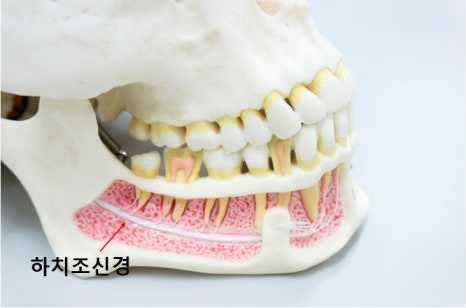

아래턱에는 하치조신경 이라는

큰 신경관이 지나가고 있습니다.

하악 임플란트 수술 진행 시

이 신경과의 거리를

정확히 확인하지 않으면

수술 후 저림이나

감각 이상이 생길 수 있습니다.

CT를 통해

• 신경의 정확한 위치

• 임플란트가 들어갈 수 있는

안전한 깊이를

미리 계산합니다.

임플란트는 한 번 심으면

되돌릴 수 없기 때문에

안전을 전제로 한 계획이

무엇보다 중요합니다.